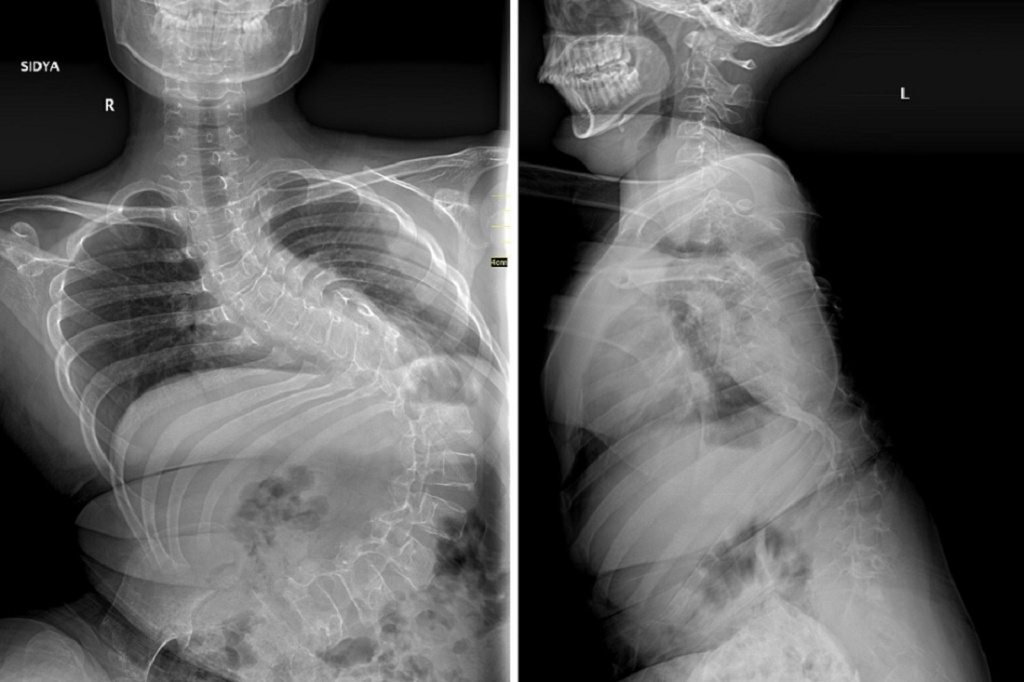

Состояние ребёнка до операции. Фото: Новосибирский НИИТО имени Я. Л. Цивьяна

Как рассказали в пресс-службе медицинского учреждения, 12-летний пациент живёт в одном из небольших сёл Тывы. Учится он в обычной школе, хотя и передвигается на инвалидной коляске, поскольку десять лет назад вместе с семьёй попал в автомобильную аварию. У ребёнка диагностировали паралитический сколиоз — тяжёлое искривление позвоночника — и выраженные неврологические нарушения.

«Первым этапом хирургического лечения стала коррекция деформации позвоночника, поскольку она достигала уже критических значений — более 140 градусов. Без своевременно выполненной операции сколиоз прогрессировал бы дальше и мальчик не смог бы даже сидеть», — описал ситуацию хирург-вертебролог Александр Васюра.

В институте отмечают, что операция прошла штатно, искривление удалось скорректировать до 32 градусов. Визуально оно всё ещё может быть заметно, но первостепенной задачей специалистов был не столько косметический эффект, сколько обеспечение комфортной жизни пациенту.